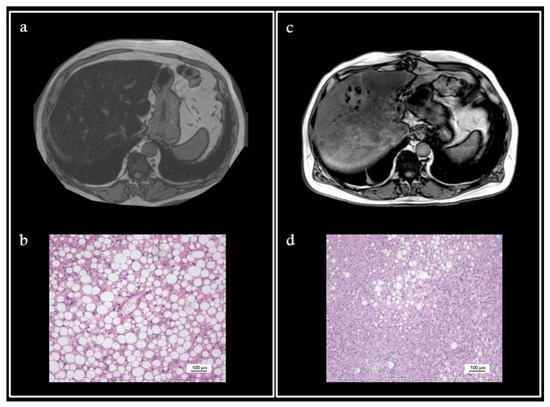

4. Illustrative Case